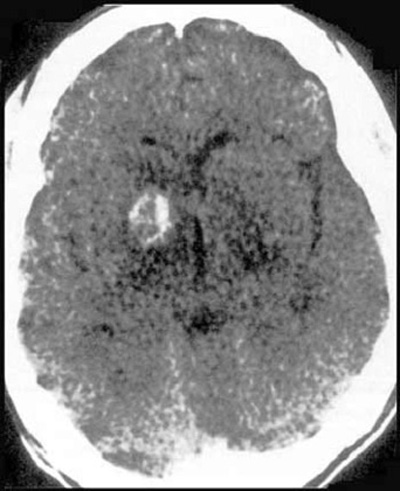

Post-contrast axial CT image of the brain at the level of the basal ganglia in a patient with h/o drug addiction.

Findings: Enhancing ring lesion within the right caudate nucleus.